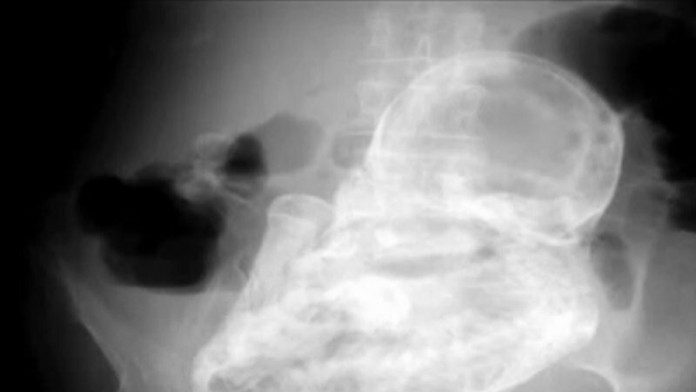

Röntgenové vyšetrenie ukázalo pravého vinníka. Lekári sa ale domnievali, že ide o nádor. Neskôr zistili, že to bol kalcifikovaný plod dieťaťa.

Takýto jav nastane vtedy, keď v tele ženy zahynie plod dieťaťa počas mimomaternicového tehotenstva. Označuje sa ako lithopedion alebo „skamenené dieťa".

Plod sa v tele dôchodkyňa nachádzal 40 rokov. Pacientku museli previesť do inej nemocnice, kde podstúpi operáciu, pri ktorej jej plod z tela odstránia.